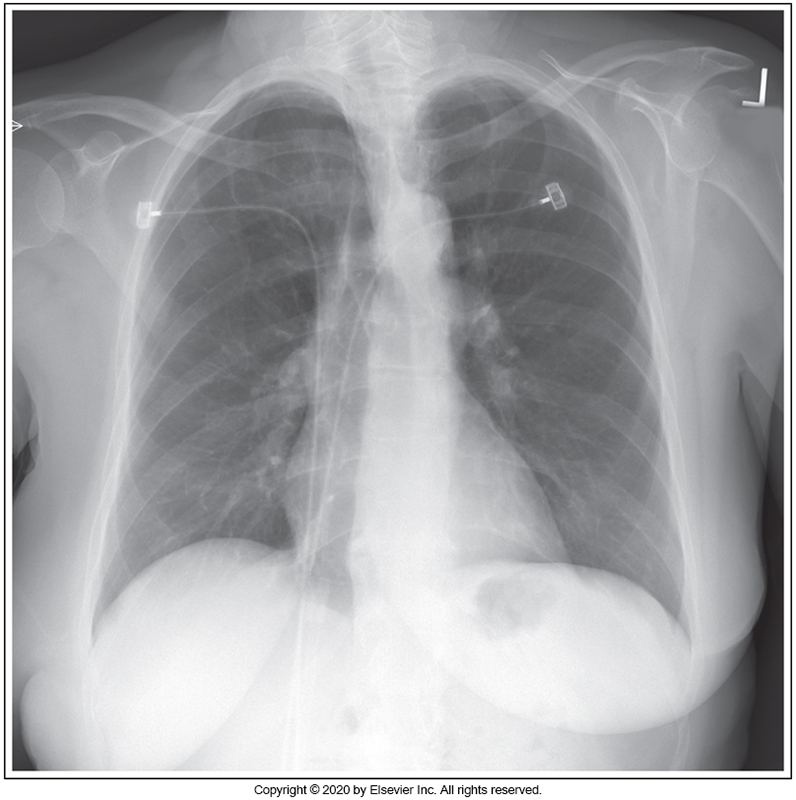

Identify the main problem of the image below (PA chest)

Patient is in an RAO position

Patient is in an LAO position

Patient upper thorax is tilted anteriorly.

Patient's upper thorax is tilted posteriorly.